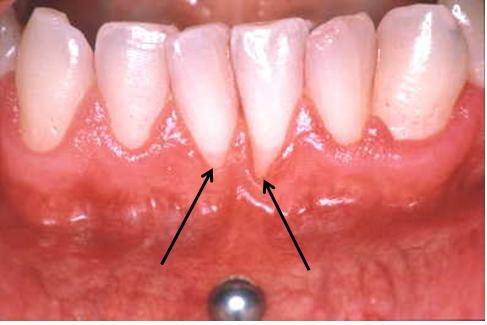

Le recul des gencives, séquelle la plus fréquente

Au même titre que les boucles pour oreilles percées, les piercings

de la langue sont maintenus sur le côté intérieur de la lèvre ou sous

la langue par un fermoir. Ces petites plaquettes ou boules blessent

les dents, les gencives et la muqueuse buccale. Parmi les séquelles

que mentionne le plus fréquemment Andrea Mombelli figurent les

blessures des gencives à hauteur des incisives inférieures, qui

peuvent entraîner, au bout de quelques mois déjà, un recul des

gencives et une mise à jour des collets. En outre, en cas de piercing

de la langue, les billes métalliques peuvent percuter l'émail

dentaire et, ainsi, engendrer des fissures et des éclats.